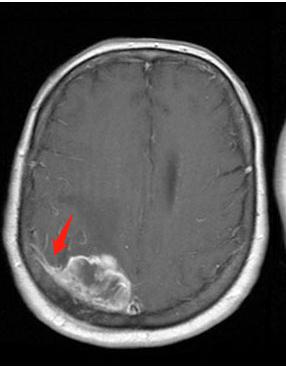

由于这种肿瘤起源于蛛网膜,所以在磁共振检查上面,我们能够看到肿瘤有条“小尾巴”,这是脑膜瘤连在蛛网膜上的“根”

这是位于嗅沟的脑膜瘤

位于额叶的巨大脑膜瘤